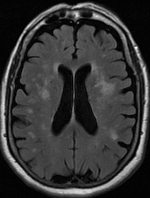

Fazekas grades. T1 t2 Flair. MRI t1 t2. T1 t2 мрт. T1 t2 fleur мрт.

Fazekas grades. T1 t2 Flair. MRI t1 t2. T1 t2 мрт. T1 t2 fleur мрт.